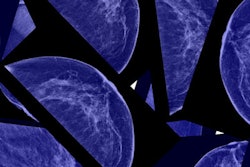

Onsite will offer MammoScreen across its more than 150 locations, the two firms said. It incorporates deep learning to help radiologists identify mammographic abnormalities that can be missed during manual review and has shown the ability to detect 42% of cancers one year prior to diagnosis and 38.5% two years prior, according to Therapixel.